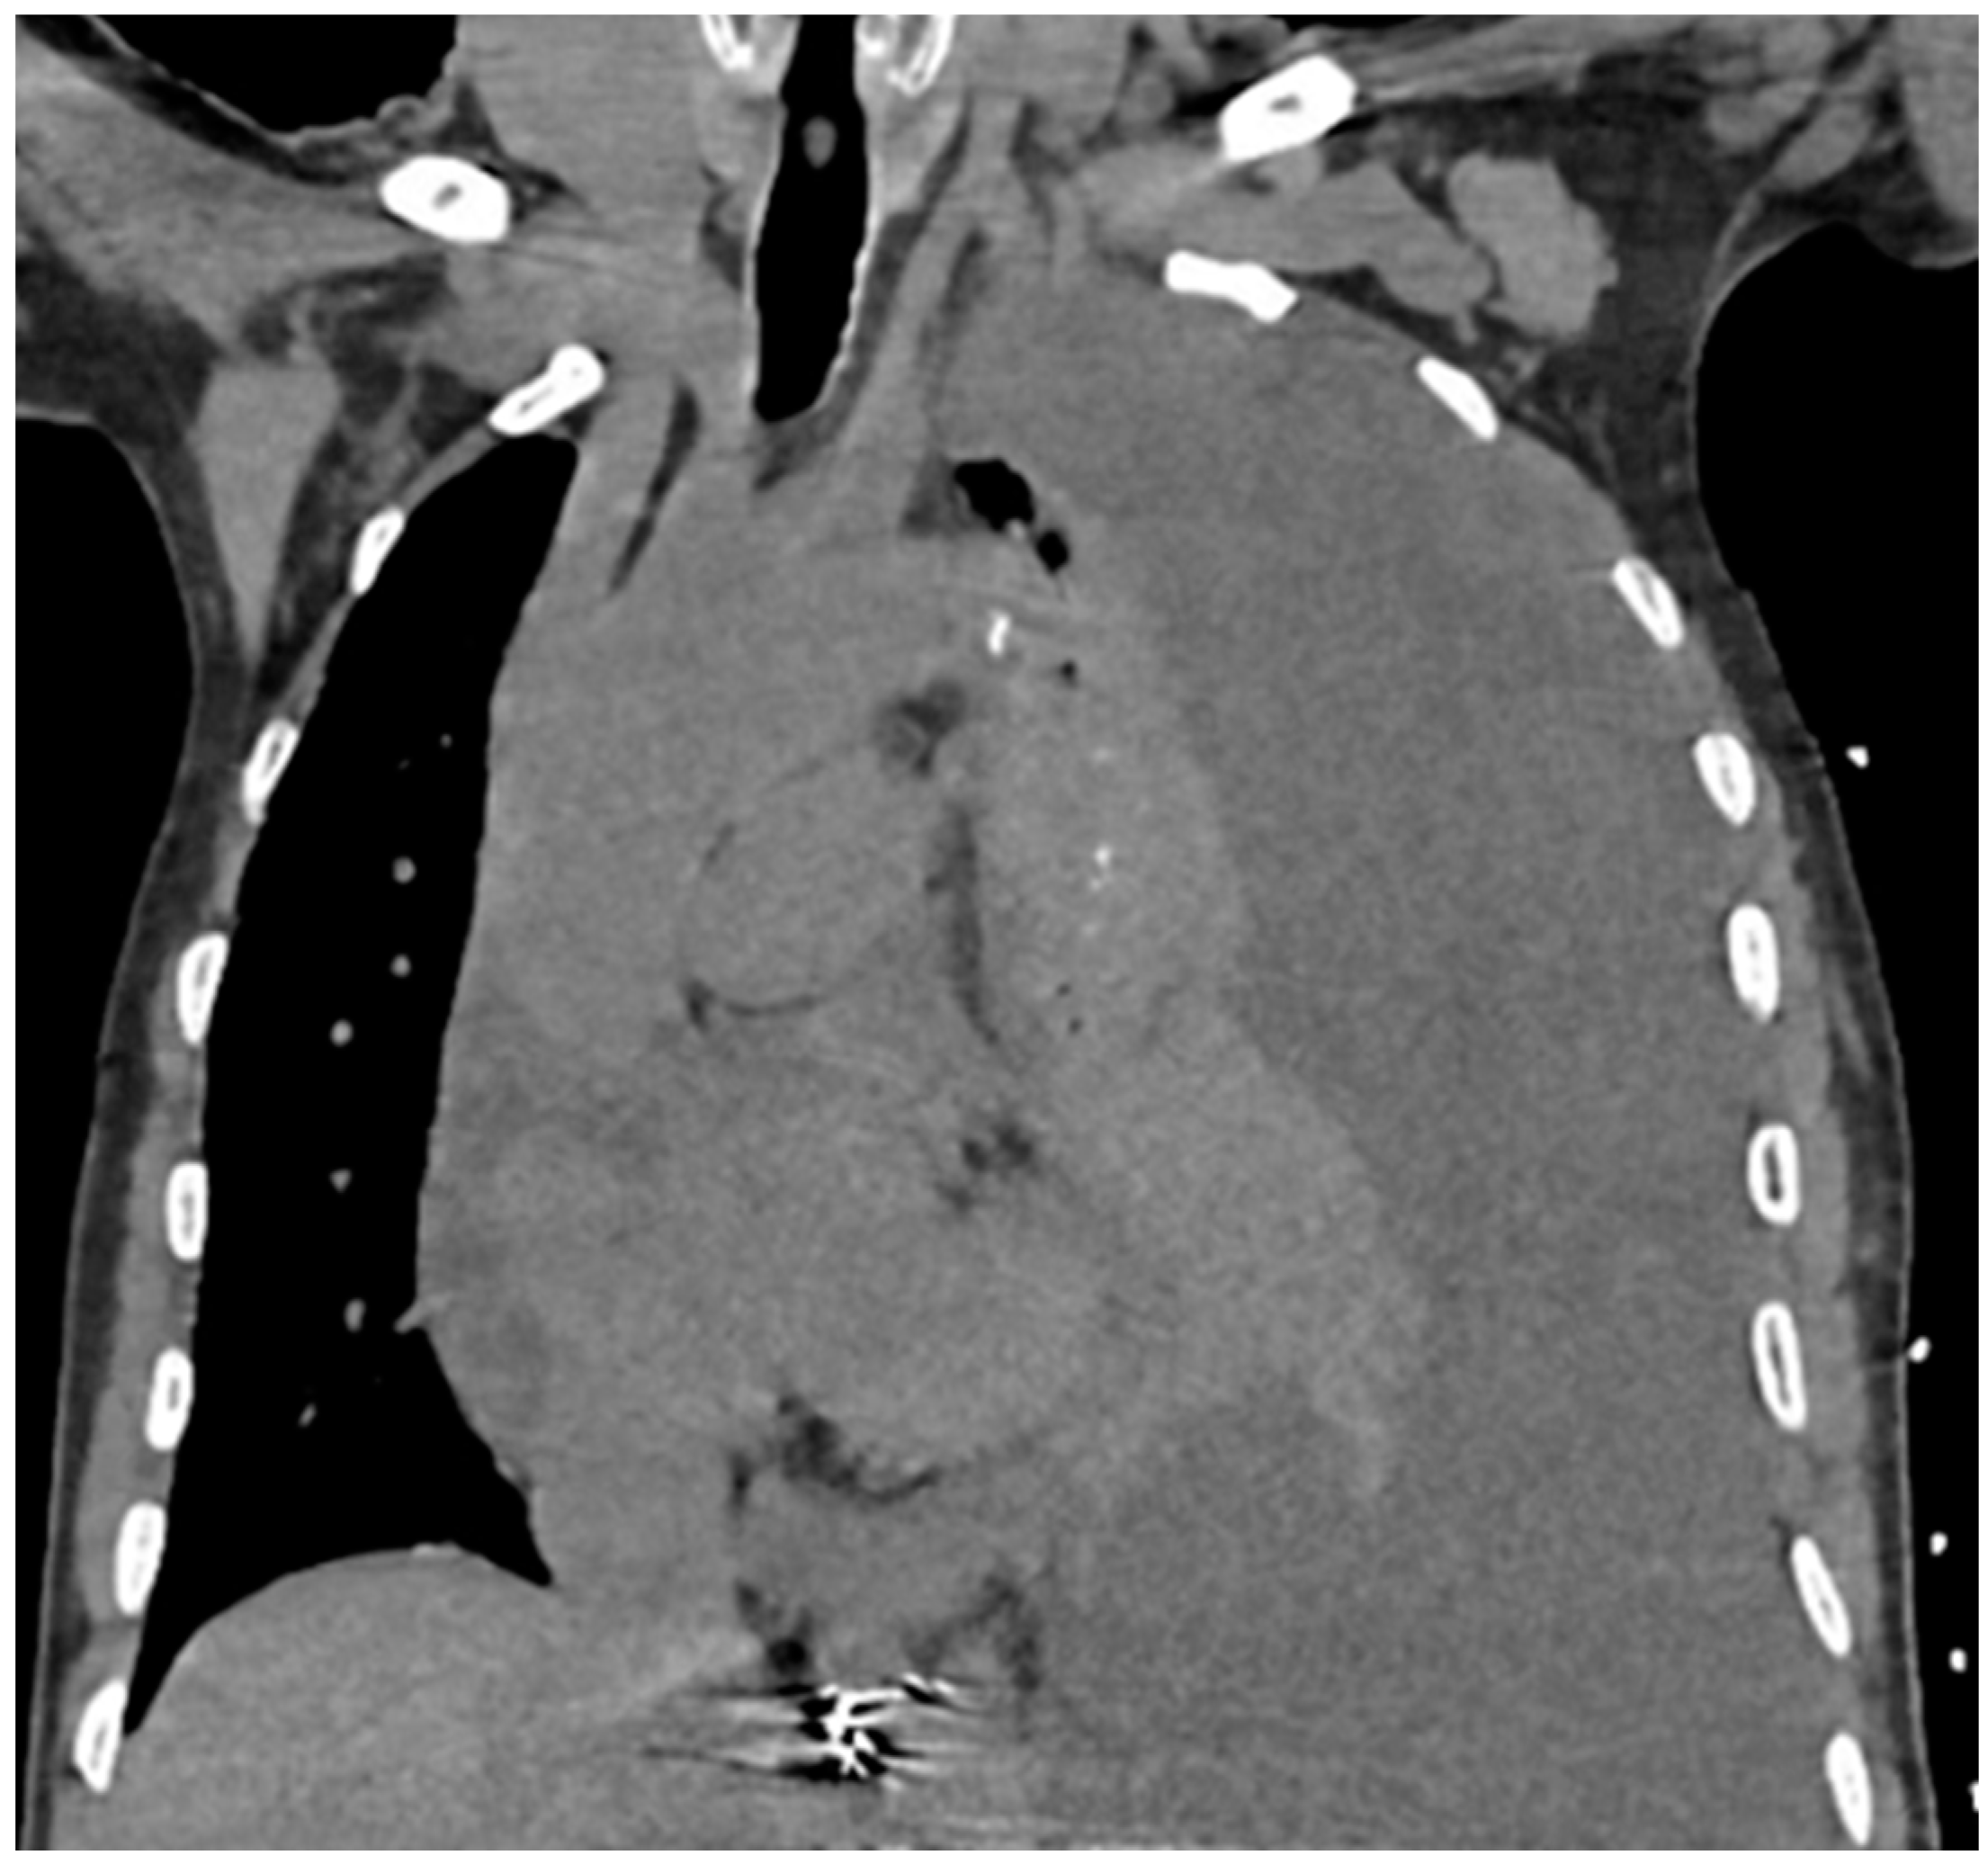

Chest X-ray (CXR) and computed tomography (CT) chest revealed a massive left-sided pleural effusion with mediastinal shift, concerning for tension hydrothorax as depicted in Figure 2 and Figure 3. Additionally, the CT scan revealed pleural nodularity with calcification on the left side without surrounding osseous involvement.

Figure 3. Coronal view of CT scan of the chest demonstrating large left pleural effusion with tracheal deviation and mediastinal structures shifted to the right.